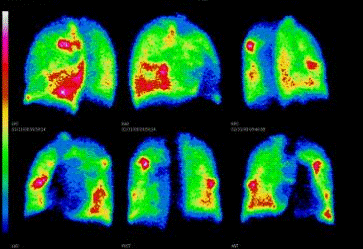

Легкие

·              Ангиография.

·              Сцинтиграфия.

·              Томография.

Одна из самых высокочувствительных методик для выявления тромбоэмболии легочной артерии и ее ветвей. Оценка кровотока по системе легочной артерии при различных заболеваниях легких.

Рисунок 10.Радионуклидная диагностика легких